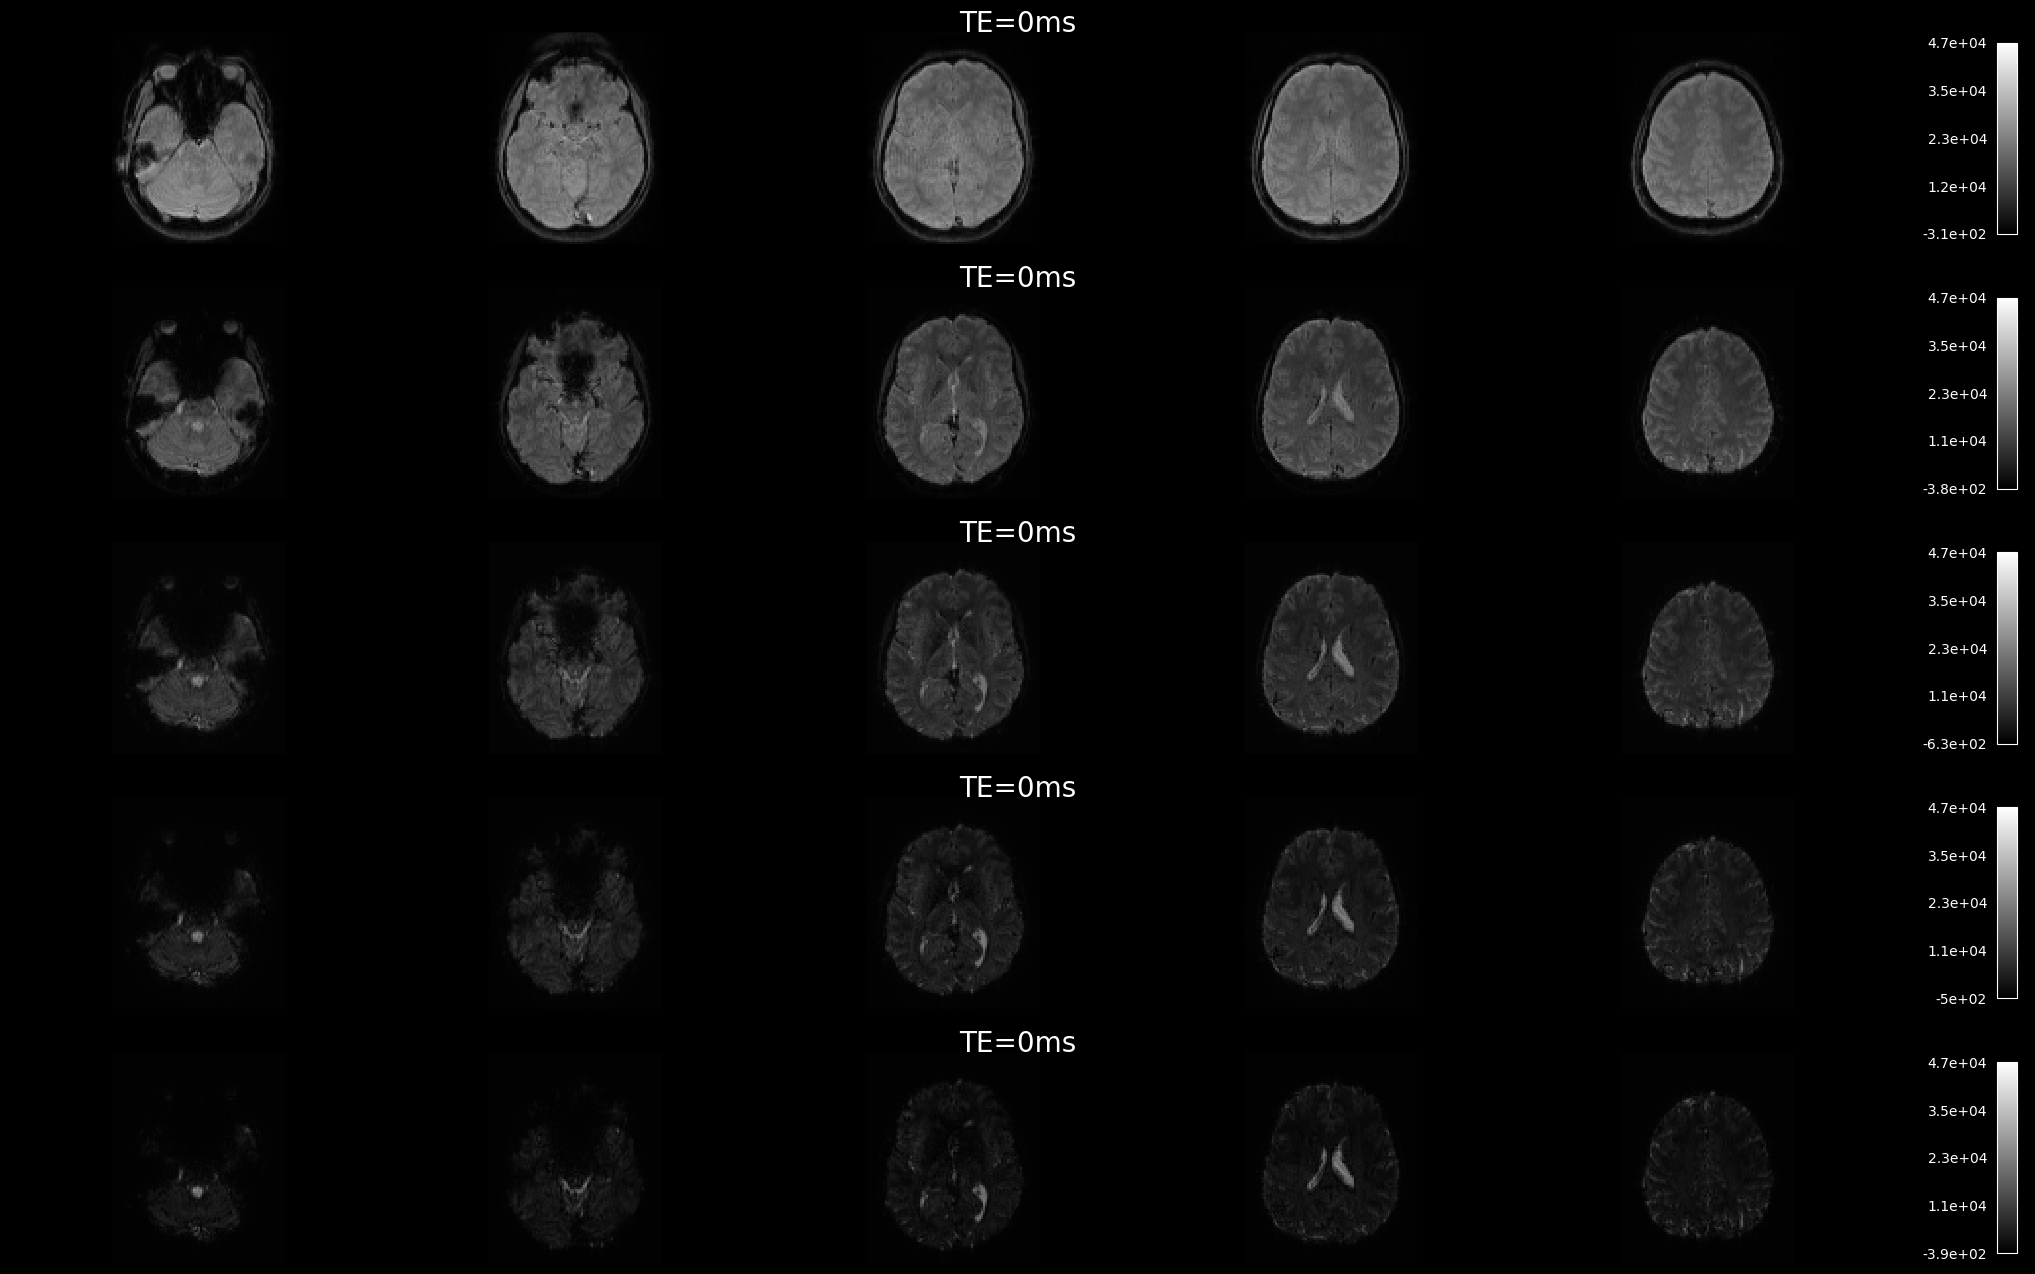

To start, let us look at how BOLD signal changes with increasing echo time in real data. The data we use is a single resting-state run, with echo times of 12, 28, 44, and 60 milliseconds.

Fig. 3 Signal decay in the brain.#

The nature of multi-echo (ME) acquisition leads to signal decay, with high signal-to-noise ratio (SNR) at short echo times (TE) and lower SNR at longer TEs. You may notice that the images appear darker as the signal decays with increasing TE. Additionally, image contrast tends to increase with longer echo times.